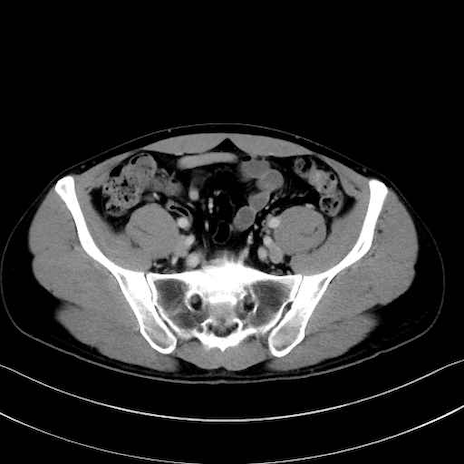

4. 深層外旋六筋(股関節の深部)

梨状筋 (Piriformis)

内閉鎖筋 (Obturator internus)

外閉鎖筋 (Obturator externus)

大腿方形筋 (Quadratus femoris)